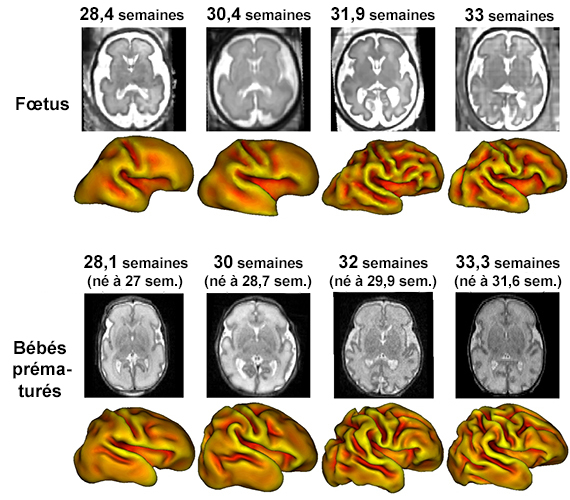

Il ressort des indices descriptifs que les nouveaux-nés prématurés ont un cerveau nettement plus plissé que celui des fœtus du même âge ce qui corrobore l’expertise des radiologues (voir figure 2). Néanmoins les vagues d’apparition des plis ne semblent pas différer d’un groupe à l’autre. Les résultats de cette étude suggèrent donc que la différence de milieux (in versus ex utero) pourraient être à l’origine de ces différences morphologiques observées. Ces résultats ont déjà été présentés au congrès européen de résonance magnétique nucléaire.

cerveaux comparaison

Figure 2 : IRM et reconstruction du modèle 3D de cerveaux pour des fœtus en haut et des prématurés d’âge de conception équivalents en bas.

Après ce travail important sur la création et la comparaison de ces modèles 3D, l’équipe de chercheurs souhaiterait mieux comprendre l’origine des différences observées. Plusieurs observations sont en effet flagrantes, comme par exemple le fait qu’il y ait beaucoup plus de liquide céphalo-rachidien (partie blanche des IRM de la figure 2) chez les fœtus que chez les prématurés. Travailler sur des IRM d’un même enfant juste avant sa naissance et juste après permettrait également de mettre en lumière les conséquences physiologiques de l’accouchement.